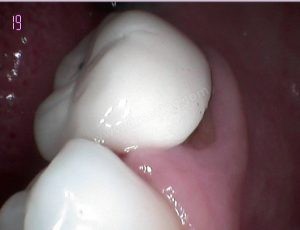

4. Dişeti Problemleri: Eski diş kaplamaları, dişetlerinde çekilmeye veya iltihaplanmaya neden olabilir. Bu durumda, diş kaplamaları çıkarılarak dişeti problemlerinin tedavi edilmesi ve ardından yeni kaplamaların uygulanması gerekebilir.

2. Diş Hazırlığı: Eğer değişim gerekiyorsa, eski kaplamalar çıkarılır ve dişlerinize uygun şekilde hazırlık yapılır. Bu süreçte dişlerinizin şekli ve boyutu, yeni kaplamaların uyumlu bir şekilde yerleştirilmesi için uygun hale getirilir.

5. Yeni Kaplamaların Yerleştirilmesi: Yeni diş kaplamalarınız laboratuvardan geldiğinde, diş hekiminiz bunları dişlerinize yerleştirecektir. Kaplamaların uyumu ve estetiği kontrol edilecek ve gerekli ayarlamalar yapılacaktır.